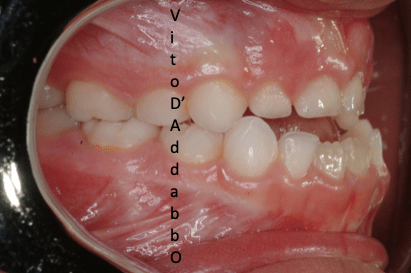

In alcune malocclusioni i denti superiori non coprono adeguatamente quelli inferiori con la presenza in alcuni casi di una beanza fra le due arcate. Questo può essere dovuto ad abitudini viziate come il succhiamento del dito, una deglutizione scorretta, una postura della lingua alterata o un problema scheletrico. In questo esempio il problema è associato ad una terza classe scheletrica.

prima